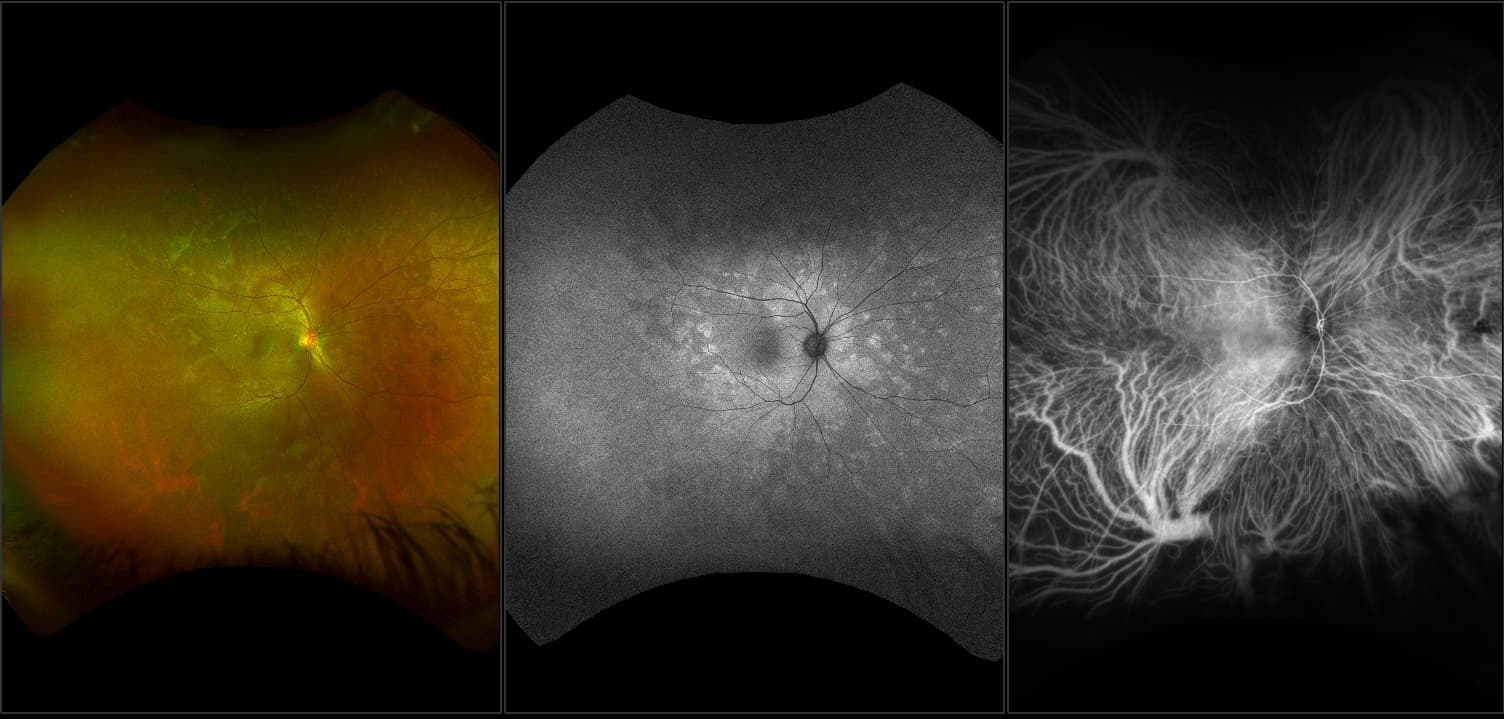

Studies have found that 97% of AMD patients have drusen in the periphery and concluded that “documentation of such finding may have implications regarding the risk of visual loss in AMD patients. AMD is NOT confined to the posterior pole” (Chew, et al. Peripheral Retinal changes associated with AMD in the Age-related eye disease study).

The recommended modality for utilizing optomap to visualize drusen, the green channel (which is captured with optomap color images).

Peripheral Changes Found in 97% of Patients with AMD Imaged with optomap in the Reykjavik and OPERA studies

Phenotyping the retinal periphery using the categories defined by the International Classification confirmed the presence of wide-ranging AMD-like pathologic changes (97%) even in those without central sight-threatening macular disease. Based on our observations, we propose here new, reliably identifiable grading categories that may be more suited for population-based UWFI.

Evaluation of Peripheral Retinal Changes on Ultra-Widefield Fundus Autofluorescence Images of Patients with Age-Related Macular Degeneration.